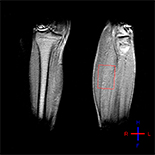

We enrolled 13 patients with stroke symptoms and hemiplegia. Lower-limb motor status on the affected side was evaluated by FMA-LE and MMAS. The 31P-MRS measures included phosphocreatine (PCr), inorganic phosphate (Pi), PCr/Pi, and pH. We statistically compared these measures in the affected and unaffected lower leg muscles before rehabilitation and after rehabilitation on the affected side. Spearman correlational analyses was performed to determine correlations between change in energy metabolism and change in FMA-LE score and MMAS score after rehabilitation.

PCr and PCr/Pi were significantly lower in the affected muscle compared to the unaffected muscle; however, there were no significant differences in Pi or pH. After rehabilitation, PCr, Pi, PCr/Pi, and pH did not significantly change. However, FMA-LE and MMAS score improved significantly after rehabilitation. Changes in energy metabolism measured by 31P-MRS had no correlation with FMA-LE change after rehabilitation. However, changes in PCr and PCr/Pi were correlated with change in MMAS score after rehabilitation.